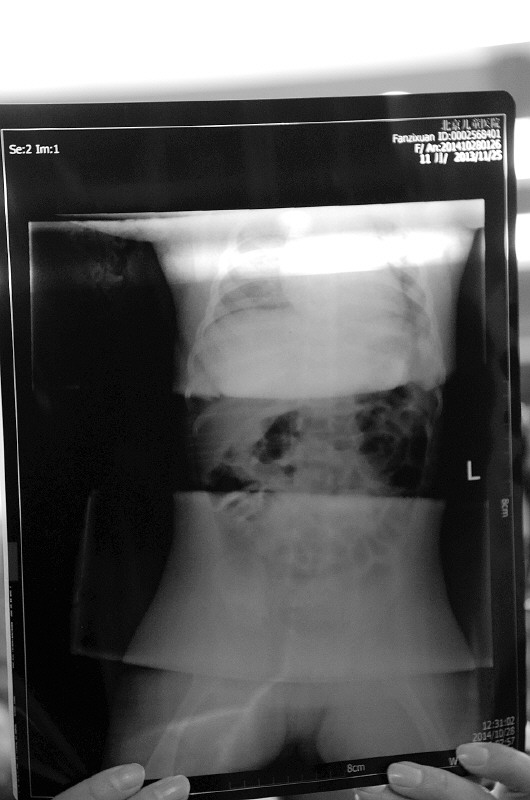

▲术后X片显示,子萱体内已没有钢针。

本报通讯员 杨建军 摄

手术结束后,医院立刻为小子萱拍了一张片子,显示小子萱体内12根针已经全部被取出,且无任何残留。张学军还介绍,这12根针中有10根是注射器针头,两根是普通的缝衣针。此前,刘玉香说自己在子萱大腿处拔出过空心的医用针头。